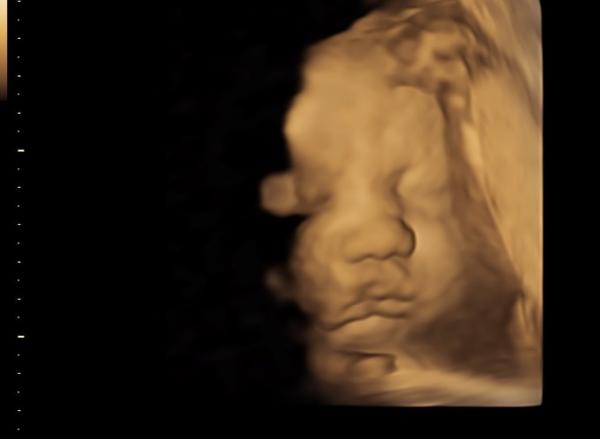

Ich war am Mittwoch beim FA , sie meinte auch das wird ein großes Kind 2300 Gramm und 42cm bei 32+5 Ein schönes Bild gab es auch noch

Bild zu